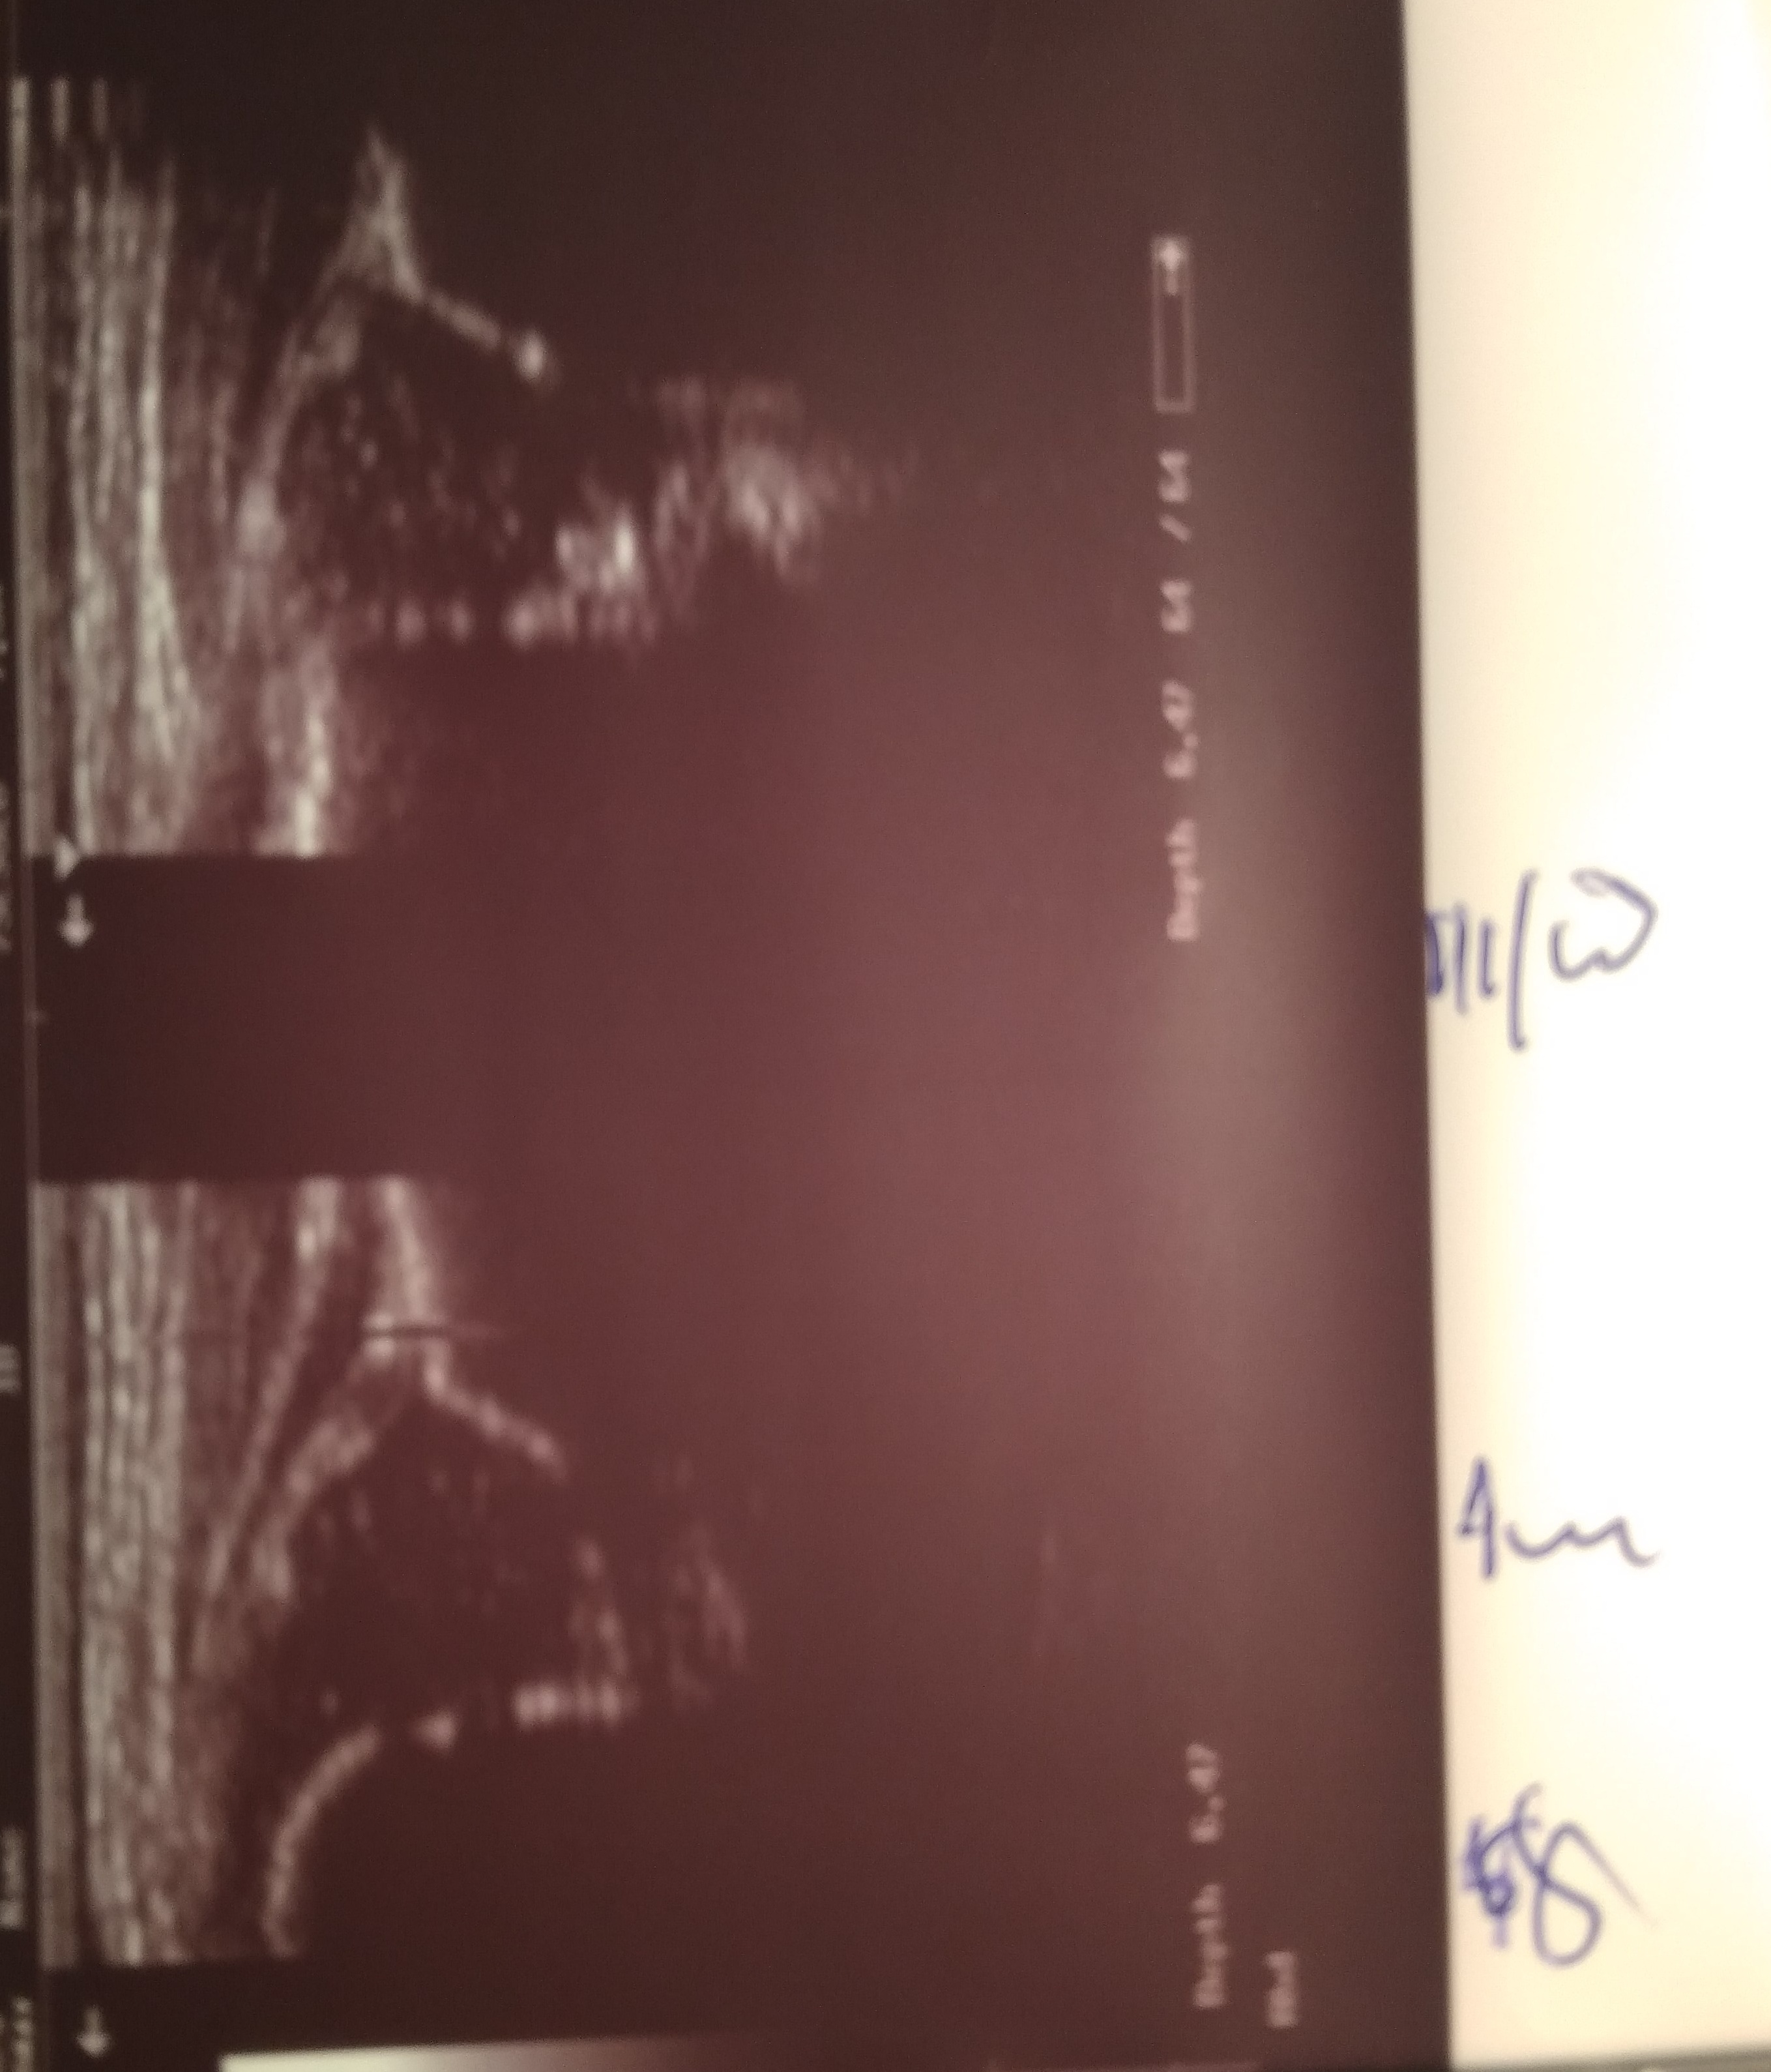

21 dzien dalej profilatyka 17 gdozin dziennie( jedna kontrola 14 dzien brak dokumentacji w ! dzien śwąt)

TYP P IIa L IID kontrola za tydzien